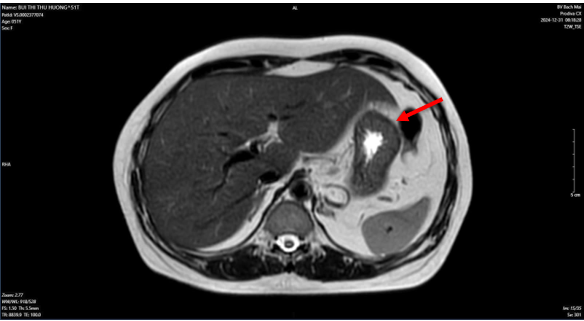

- Chụp cắt lớp vi tính ổ bụng: Không phát hiện tổn thương bất thường.